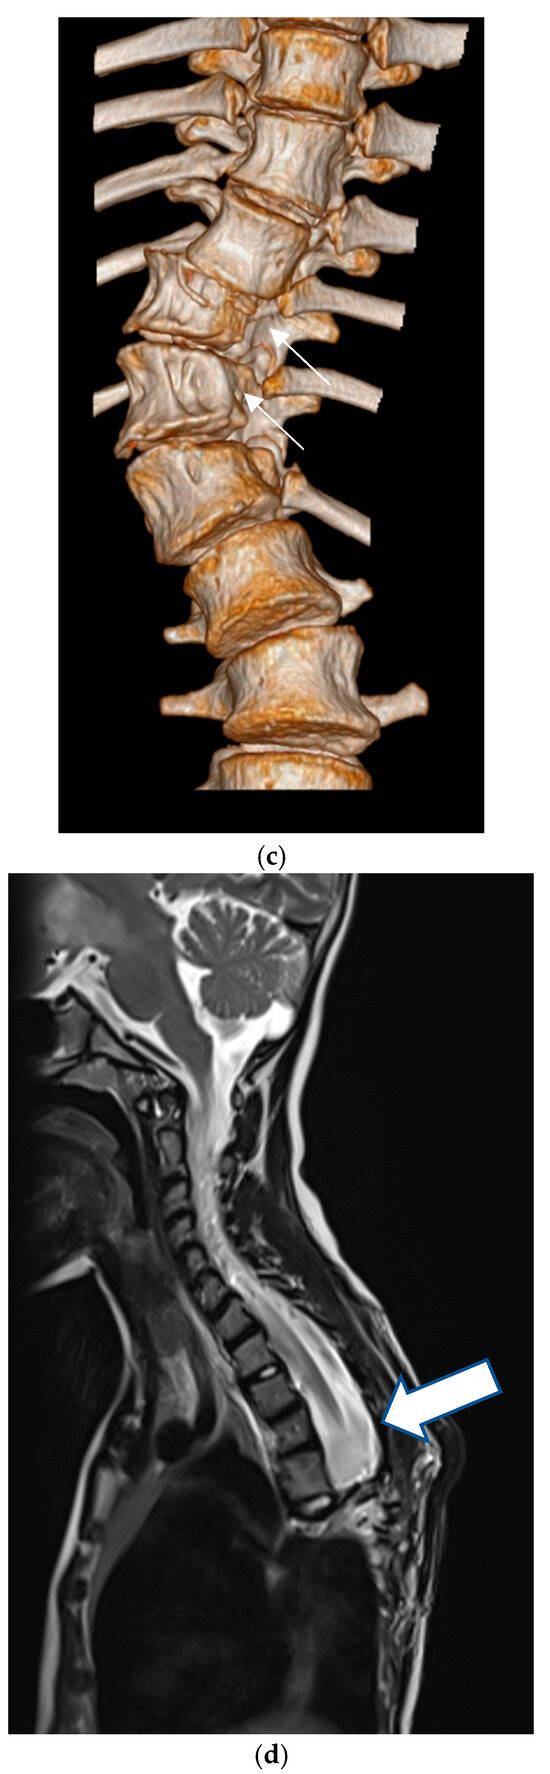

4.1. Cervical Spine

5.1. Cervical Spine